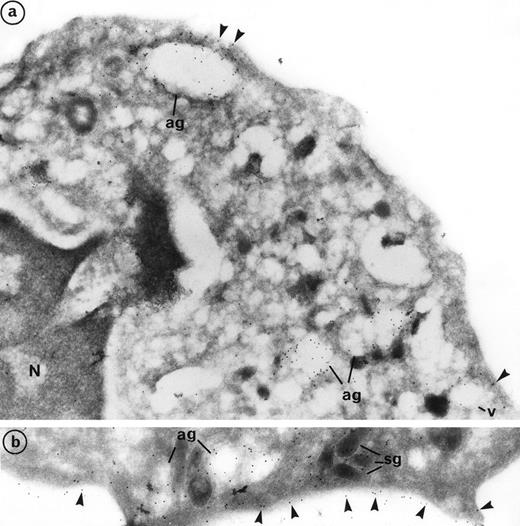

Labeling of PR3 with the mouse monoclonal CLB 12.8 showed immunogold grains on the plasma membrane as well as within intracellular granular compartments. PR3 labeling was also observed at the periphery of large extracted granules, the azurophil granules (ag), and empty vesicles (v) (Fig 3a). Plasma membrane labeling of PR3 was homogeneous on the cell surface and was not restricted to certain areas (Fig 3b). However, the intensity of this labeling varies from one neutrophil to another, thus confirming the heterogeneity of PR3 membrane labeling measured by flow cytometry using the same antibody CLB12.8. In the donor that we present in Fig 3, 80% of neutrophils were positive for PR3 membrane labeling and 20% were negative. However, all neutrophils showed azurophil granule labeling. Figure 3a shows a neutrophil with weak PR3 membrane labeling, although azurophil granule labeling was present. Figure 3b shows a neutrophil with intense PR3 membrane labeling.

Subcellular localization of PR3 by electron microscopy on neutrophils thin frozen sections labeled with anti-PR3. Electron micrograph of resting neutrophils from the same individual stained for localization of PR3 with the MoAb anti-PR3 CLB 12.8 followed by incubation with 10-nm gold particles-conjugated goat antimouse (GAM 10). (a) Gold-labeled antibody is present at the periphery of large extracted granules identified as the azurophil granules (ag) as well as in the membrane of intracellular empty vesicles (v). Plasma membrane labeling is shown by arrow heads (original magnification × 35,200). (b) The immunogold label (arrowheads) indicates the presence of PR3 on the plasma membrane in a random distribution head (original magnification × 42,550).

Double labeling of PR3 with MPO confirmed that PR3 is located with MPO in the azurophil granules (ag) that represent the major intracellular store of PR3 (Fig 4a). Azurophil granules appeared as large empty extracted granules with strong intragranular MPO labeling. Previous electron microscopy studies have pointed out the particular trend of azurophil granules to be extracted, which made them look lighter than the other granules.33 Azurophil granules were abundant and in clusters within neutrophil cytoplasm. PR3 labeling was mainly restricted to the periphery of granules. In contrast to MPO, PR3 labeling also appears in the membrane of small empty vesicles (v). PR3 labeling can be detected in the limiting membrane of some dense and small granules, with an elongated form characteristic of specific granules (sg) (Figs 3b and 4a, b, and d). This labeling was weak but appeared to be significantly higher than background labeling on mitochondria taken as control. Double-labeling PR3 with lactoferrin confirmed that PR3 is present in the membrane of lactoferrin-containing granules (Fig 4b).

Evidence of the colocalization of PR3 with MPO in azurophil granules, PR3 with lactoferrin in specific granules, and PR3 with CR1 in secretory vesicles using double immunolabeling electron microscopy. (a) Double immunolabeling with the MoAb anti-PR3 CLB 12.8 coupled with a 10-nm gold particles-conjugated goat antimouse (GAM 10) and the polyclonal anti-MPO coupled with a 5-nm gold particles-conjugated goat antirabbit (GAR 5). The presence of 5-nm gold grains in large empty granules indicates that MPO is localized exclusively in azurophil granules. The colocalization of gold grains of both sizes within these granules indicates that PR3 is located with MPO in these granules. However, in contrast to MPO, PR3 is also localized at the periphery of empty vesicles (v) and in some specific granules (sg1) (original magnification × 54,250). (b) Double immunolabeling with the MoAb anti-PR3 CLB 12.8 coupled with a 10-nm gold particles-conjugated goat antimouse (GAM 10) and the polyclonal antilactoferrin coupled with a 5-nm gold particles-conjugated goat antirabbit (GAR 5) showing the presence of PR3 (arrowheads) along the limiting membrane of an elongated specific granule identified as such thanks to its prominent lactoferrin content (original magnification × 86,800). (c) Visualization of secretory vesicles with CR1 labeling. Immunolabeling of CR1 was performed with the polyclonal anti-CR1 coupled with GAR 5 and shows the localization of CR1 in the membrane of the secretory vesicles, which appear as empty organelles, but not in specific granules (original magnification × 98,700). (d) Double immunolabeling with the MoAb anti-PR3 CLB 12.8 coupled with GAM 10 and the polyclonal anti-CR1 coupled with GAR 5. Both sizes of grains are detected in the membrane of secretory vesicles identified by the presence of CR1 (original magnification × 98,700).